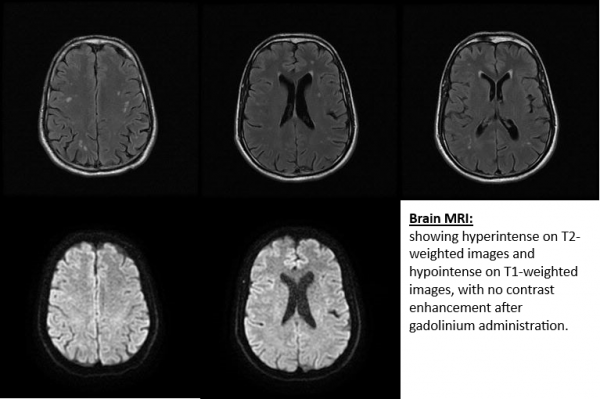

Brain and orbital MRI with contrast can confirm or exclude different forms of optic neuropathy. Typical ON demonstrates a short segment of contrast enhancement of the optic nerve and demyelinating white matter lesions for MS may be seen. Even in the absence of typical demyelinating white matter lesions at onset, patients with ON may still develop MS [4]. MS lesions on MRI are characteristically hyperintense on T2 weighted imaging, ovoid, and located in the periventricular, juxtacortical, infratentorial, and spinal cord white matter [3]. Atypical ON due to NMO may show a non-MS location of white matter lesions on the brain MRI, the optic nerve enhancement may be more posterior (optic chiasm and optic tract) and there maybe longitudinally extensive enhancement (> ½ length) of the optic nerve. In addition, patients with spinal MRI may show a longitudinally extensive transverse myelitis (greater than 3 spinal segments) [3]. Therefore, MRI can be a useful tool to differentiate between different etiologies of ON.